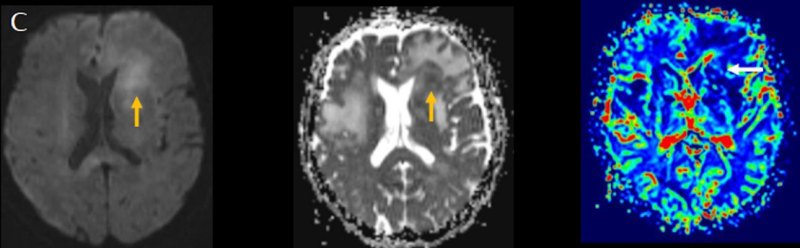

- (C) Difüzyon ağırlıklı görüntülerde sol frontaldeki kitle lezyonunda difüzyon kısıtlama bulgusu (oklar) mevcut olup perfüzyon MRG’de rCBV haritasında belirgin perfüzyon artışı izlenmemektedir (ok).

- MRG’de, lenfomalar tipik olarak T2A sekanslarda hipointens olup DAG’de belirgin difüzyon kısıtlanması gösterirler.

- T2 sinyali belirgin düşük olgularda b=1000 görüntülerde hipointens görünüm izlenebilir ve T2 kararması (T2 black-out) etkisi olarak adlandırılan bu durum yanlış yorumlamalara yol açabilir. Bu nedenle gerçek difüzyon kısıtlamasını değerlendirmede ADC haritaları daha güvenilirdir.

- Perfüzyon MRG’de düşük-orta düzey CBV değerleri izlenir. Lenfomalarda düşük CBV değerleri, kötü prognoz göstergesidir.